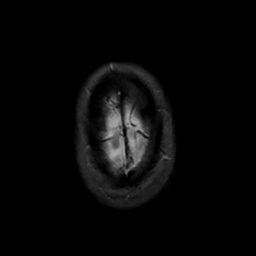

MR Study #6, March 17, 1991 -- Slice #47

[Home][Help][Clinical][Tour 1][Tour 2] Slice 47